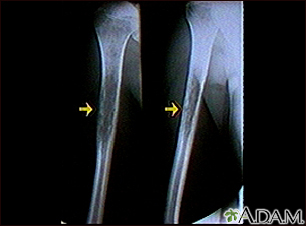

Ewing sarcoma - x-rayBackEwing sarcoma - x-rayThis x-ray shows a malignant bone tumor (Ewing sarcoma) of the upper arm bone (humerus). This type of tumor usually occurs during childhood and adolescence. E-mail FormEmail ResultsName:Email address:Recipients Name:Recipients address:Message: